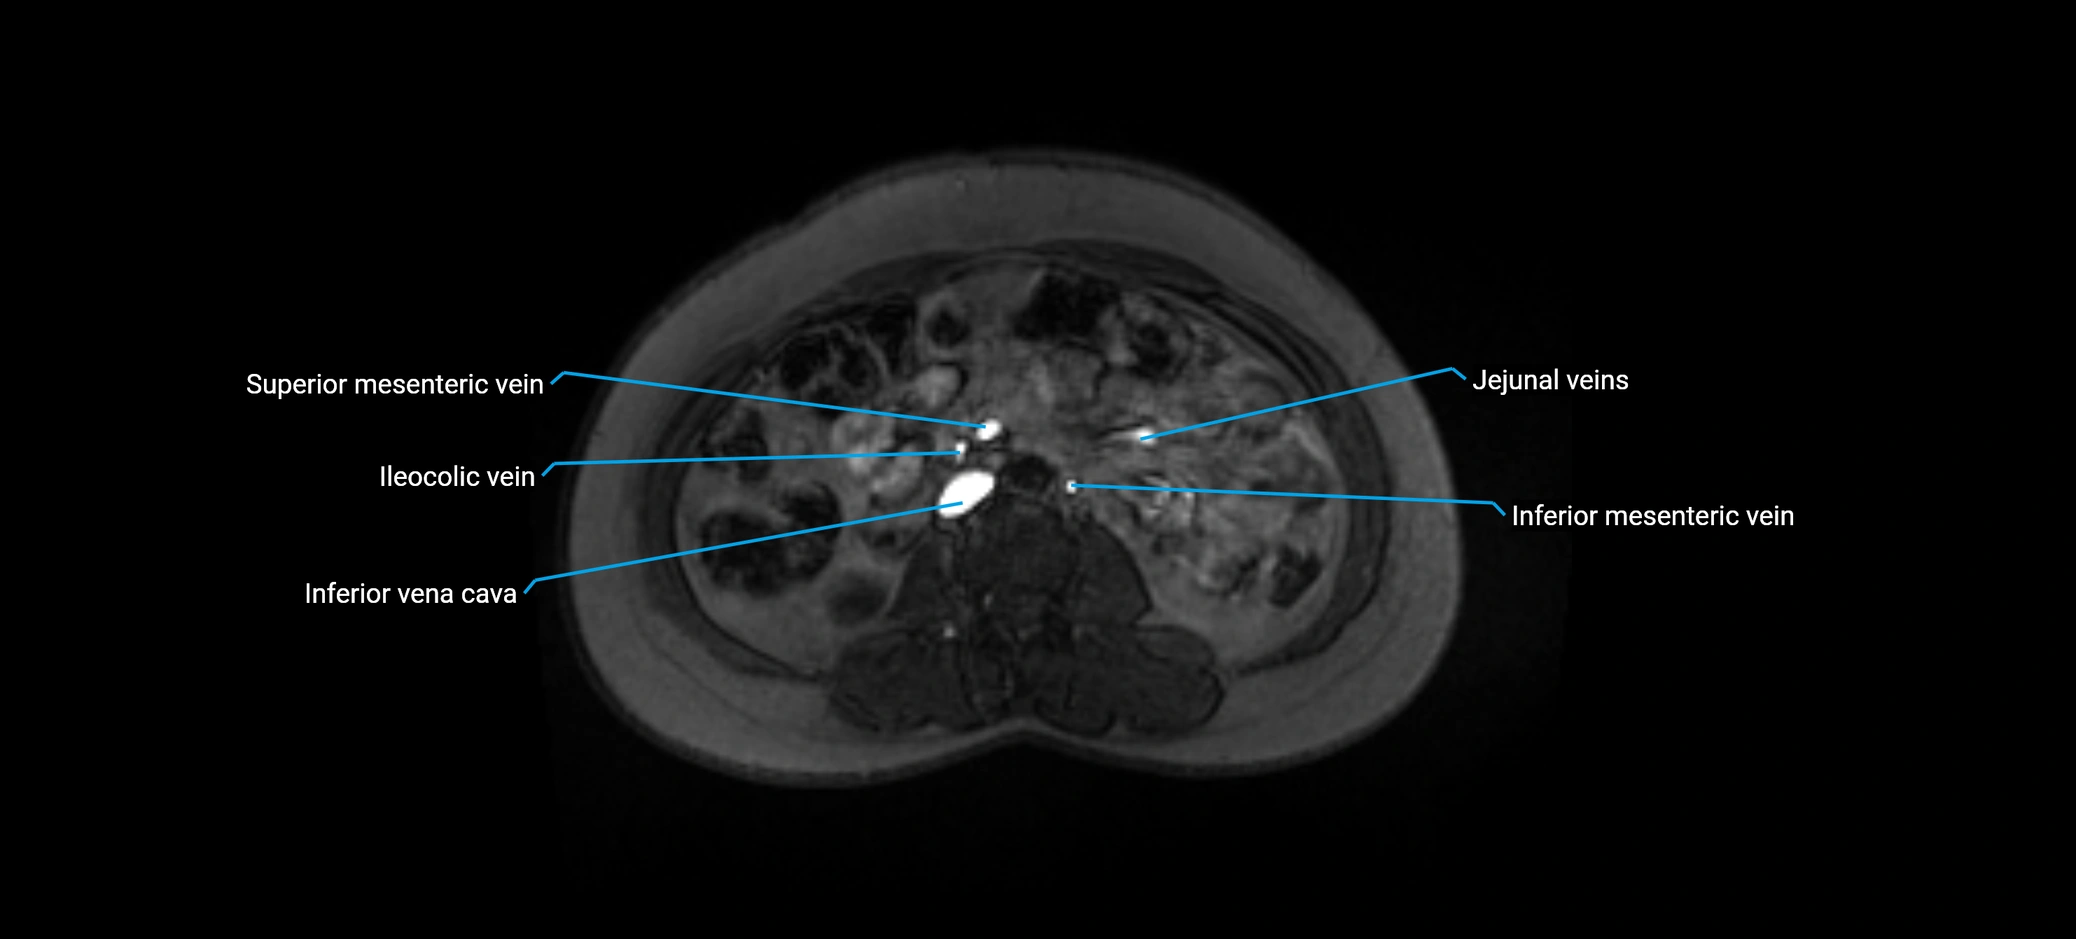

MRI image

image